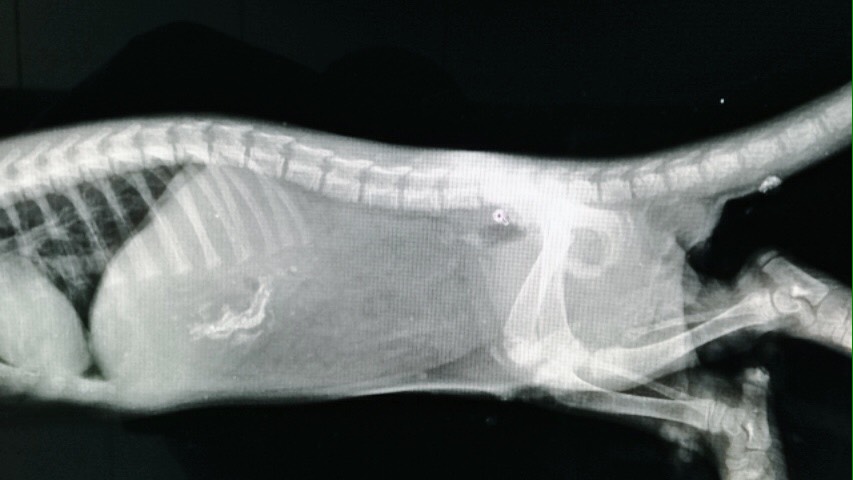

小水獺剛到獸醫院時渾身沾滿泥沙、體力較差,金門縣野生動物救援暨保育協會依程序向金門縣政府通報後,協會獸醫歐陽澍也為小水獺進行麻醉檢傷。小水獺為雄性,年齡約在2至3個月,全長約60公分,體重約1公斤,X光顯示牠的胃部有鈣質食物,根據體型與乳齒等型態判斷牠應該才剛離乳不久。